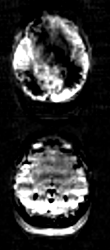

1.2 low label efficiency

- Appearance: asymmetric signal between the left and right or between the frontal and posterior regions

- Cause: head position or the labeling location is not right in the pCASL settings

- Solution: Figure 1 in http://dx.doi.org/10.1002/mrm.29572